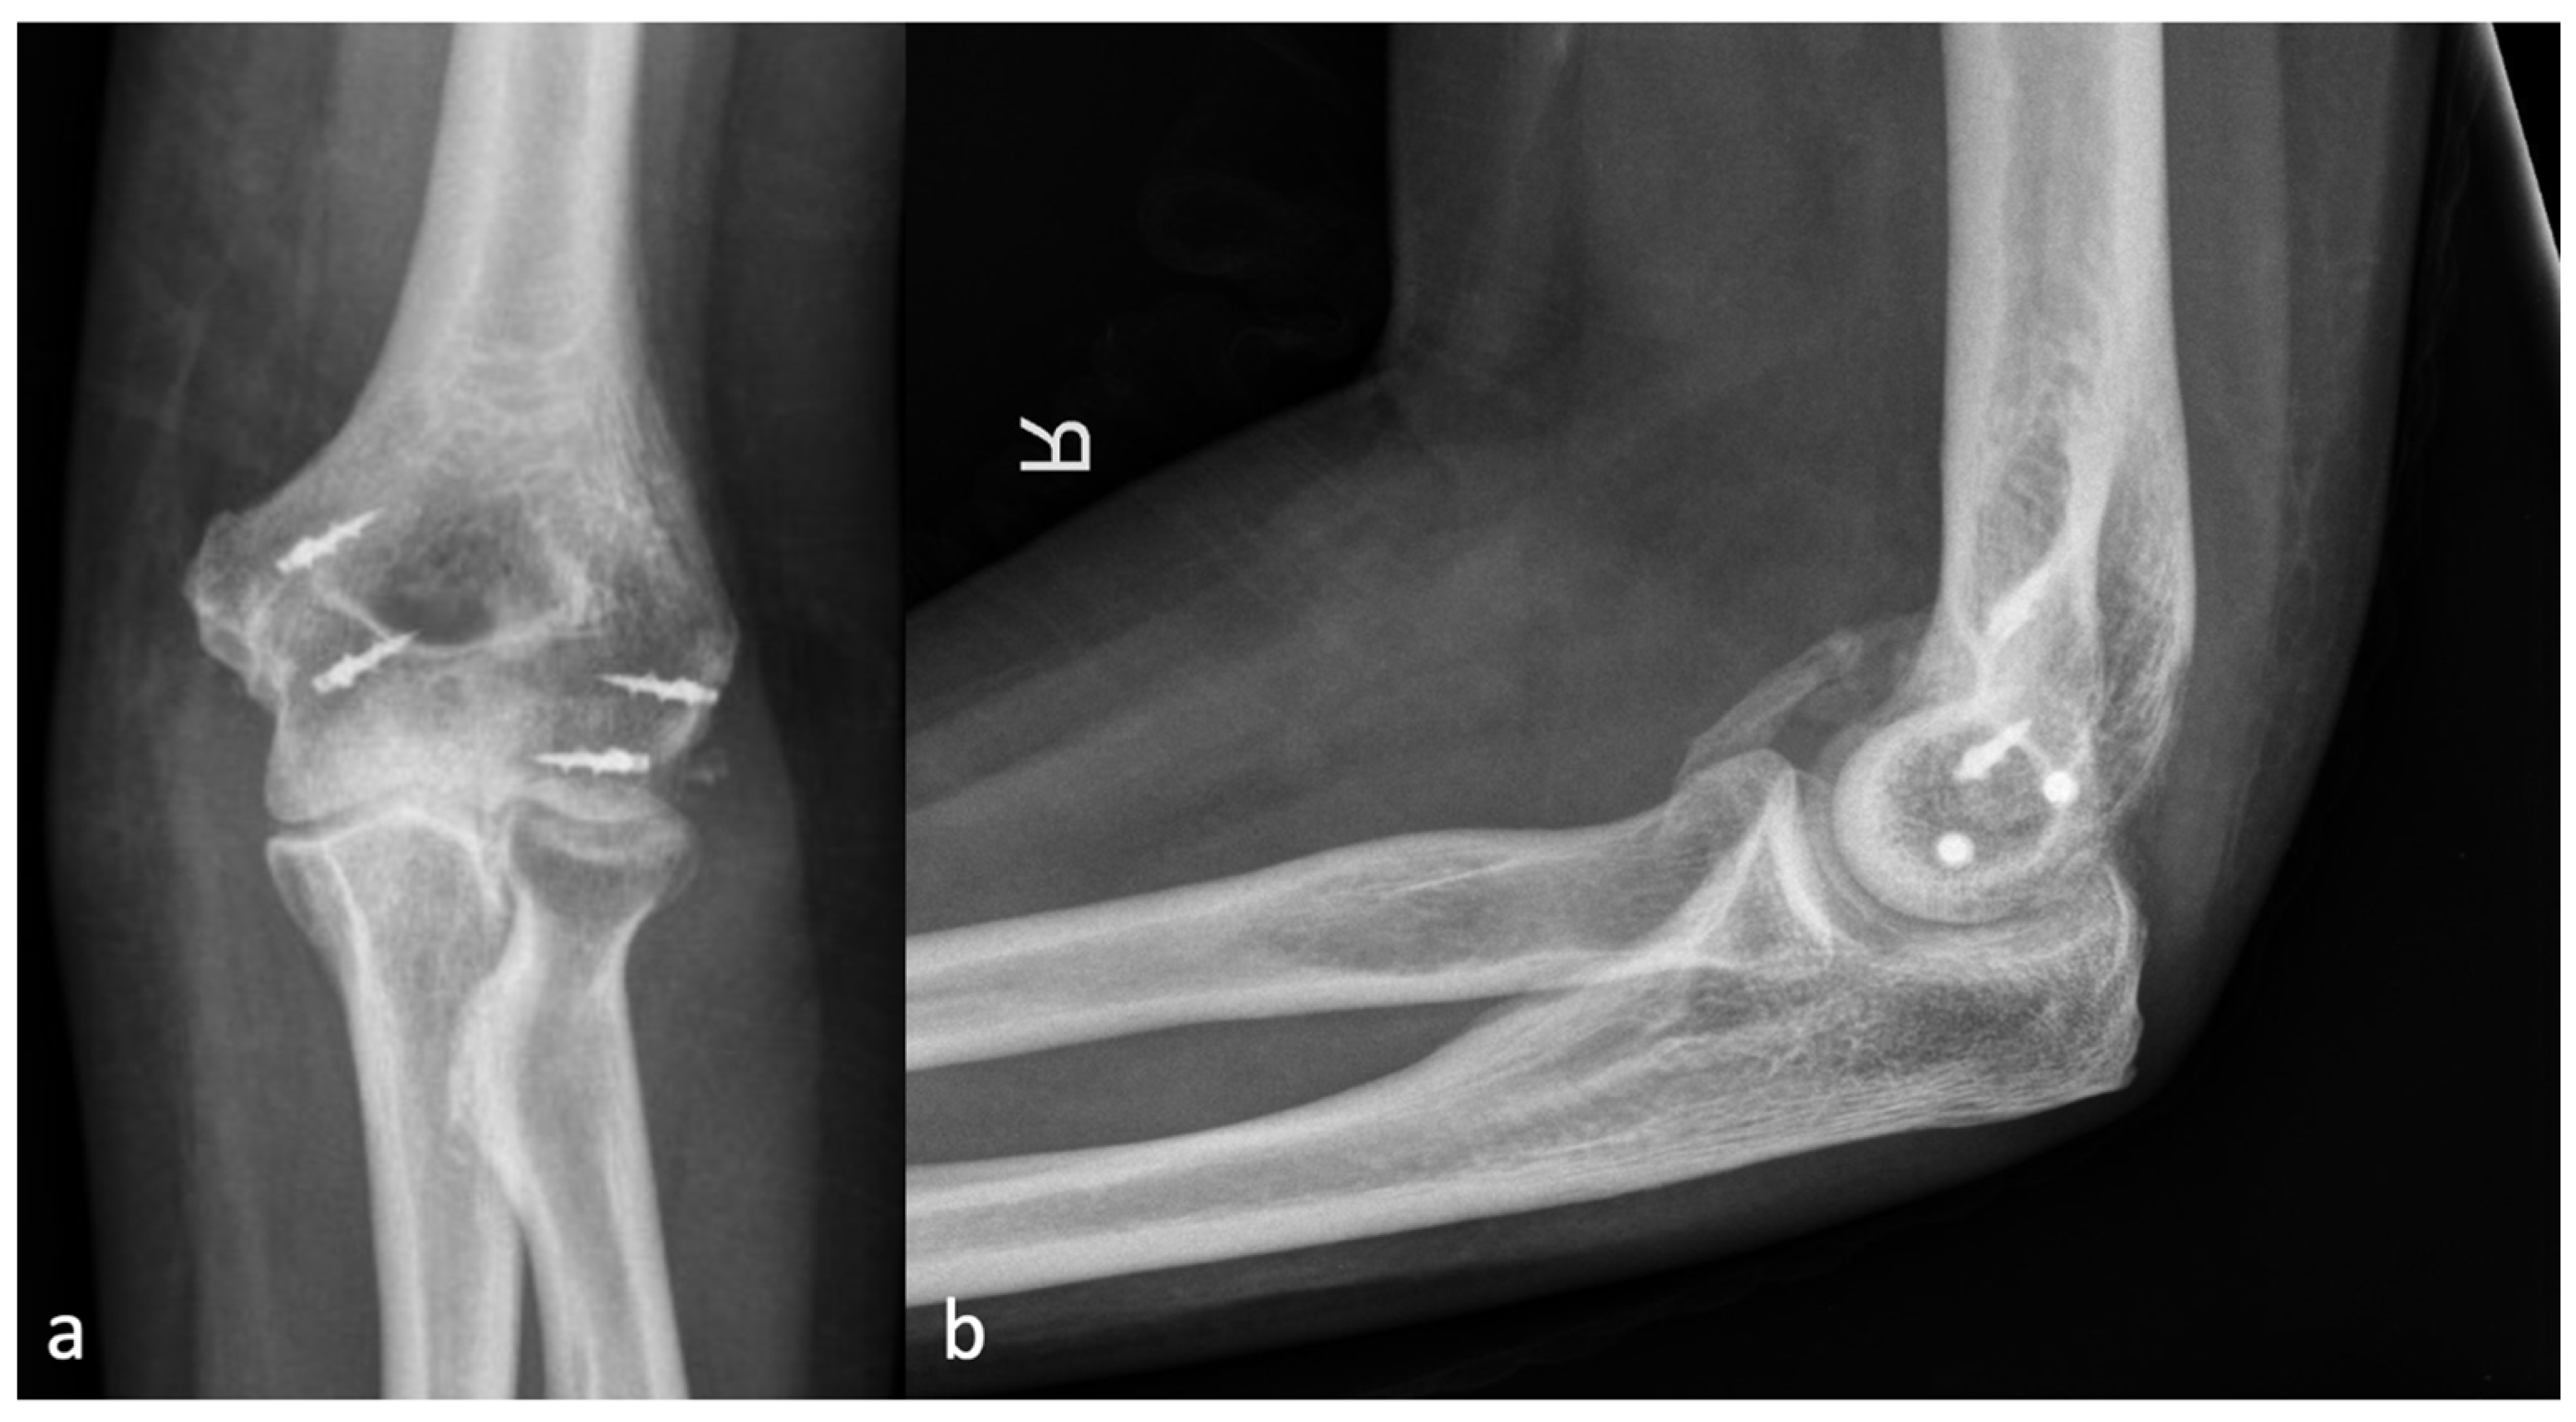

2.2. Radiographic Assessment

2.3. Classification

3.2. Relationship between Injury Localization and the Localization of HO

3.3. Correlation between the Application of Ossification Prophylaxis and the Severity of HO

4.1. Classification